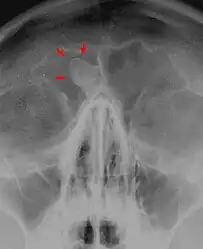

Medical imaging such as X-ray, CT scan and MRI show dense, clearly defined, round white tumors attached to bone.[1] They may be diagnosed when having medical imaging for another reason.[3] Osteomas of the paranasal sinuses and skull base can be diagnosed using CT-scan without intravenous contrast, allowing its size and relation to nearby important structures to be assessed.[3] A biopsy is not usually required.[3]

X-ray skull: Osteoma of the frontal sinus -

X-ray skull: Osteoma of the frontal sinus